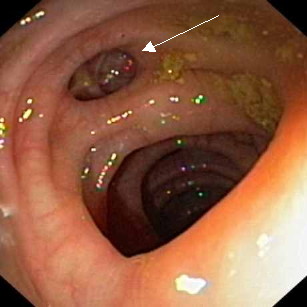

Le diverticule forme une sorte de "grotte". Il ne s’agit pas d’un orifice sinon il s'agirait d'une perforation du colon qui est une urgence chirurgicale. Vous pouvez voir un diverticule indiqué par la flèche sur la photo suivante :

Figure 3 : Diverticules visualisés lors d'une coloscopie

(Copyright GastroLab)